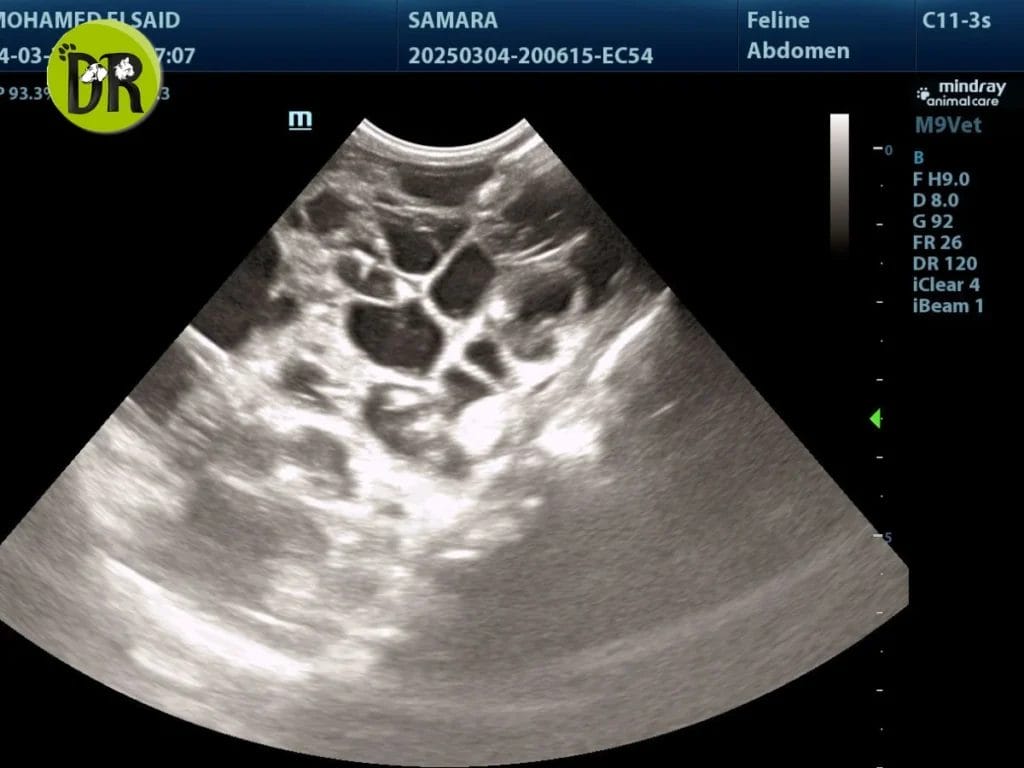

بينما كشفت الأشعة فوق الصوتية عن وجود أكياس داخل الكليتين، وهو ما أكد إصابة سمارة بمرض الكلى المتعدد الكيسات (PKD)، وهو مرض وراثي شائع بين القطط الفارسية.

يتوجه فريقنا بخالص الشكر إلى Dr. Nadia Essam على إشرافها المباشر على الخطة العلاجية، و Prof. Mohamed El-Sayed, PhD على دقته في الفحص بالأشعة وتأكيد التشخيص.